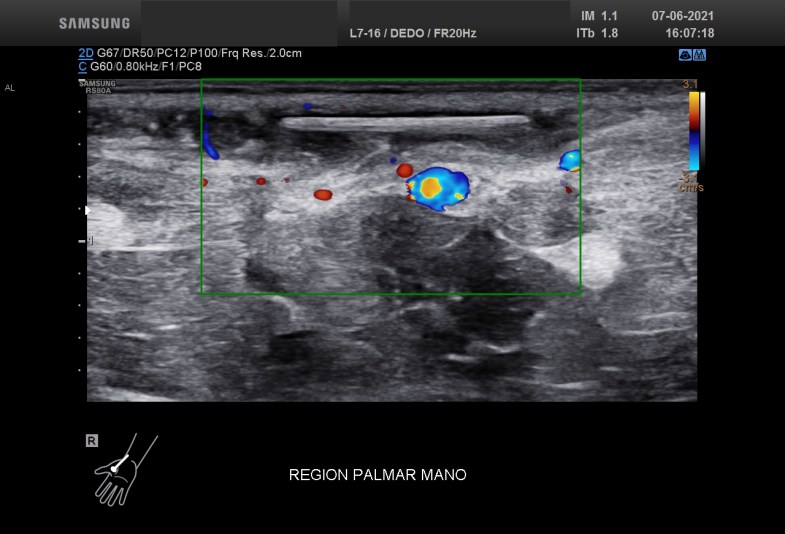

Finalmente, el doppler para demostrar vascularizaciones anómalas que este caso no existían o no pudieron ser demostradas con la técnica habitual.